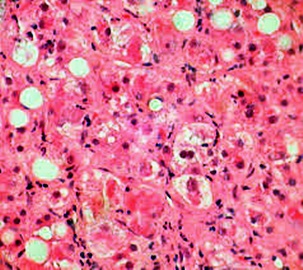

몸에 필요한 황색의 담즙색소 (빌리루빈)이 과도하게 쌓여 눈동자나 피부 등에 착색되는 현상을 말한다고 합니다. 이 담즙색소는 체내에 들어온 물질들이 분해되는 과정에서 생성되는 필요 없는 물질인데요. 일반적으로는 간에서 해독작용을 거친 후에 담즙으로 배설이 되는 것이 정상적이지만, 그렇지 못한 경우 황달이 발생하게 된다고 합니다.

황달이 생기는 이유는 담즙색소라고 알려진 빌리루빈이 과도하게 생기기 때문입니다. 빌리루빈은 우리 몸의 오래된 적혈구가 파괴되면서 생기는 물질인데요. 이 물질은 담즙에 녹아서 우리 몸의 배설물과 함께 배출이 되는 것이 정상적이지만 빌리루빈의 과잉생산이나, 간의 장애, 간세포나 담도의 손상에 의해 빌리루빈이 역류할 경우 발생된다고 합니다.